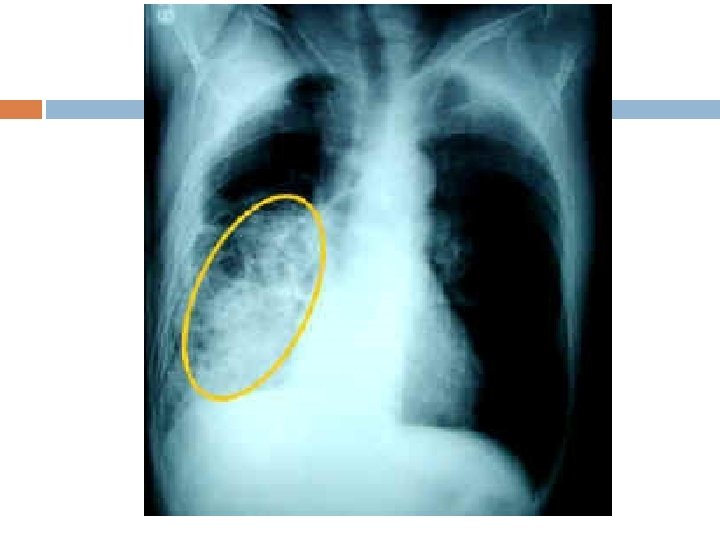

Pneumonia Inflammation of the lung: bacterial or viral may also be caused from infections that spread to the lungs through the bloodstream from other organs (50%: viral) Streptococcus pneumoniae: most common bacterial form

Symptoms/treatment Cough High Fever (104) Chest pain Shortness of breath

Tuberculosis is characterized by white lesions or tubercles which replace alveoli with scar tissue results in poor gas exchange between the lungs and the blood

Symptoms Coughing Wheezing Chest pain Fever, chills Loss of appetite Possibly death